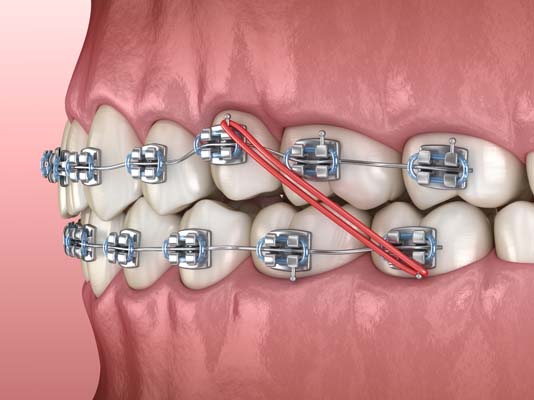

If caught early, one of the best ways to correct an overjet is with braces. Most overjets can be corrected using standard metal or ceramic braces or even clear plastic aligners. The best time to correct the issue is in early childhood before the condition can become severe or create other dental issues.

Braces and aligners work by gradually shifting the teeth into position over time until they are straight. Typically, braces are installed over the teeth and are adjusted manually by your dentist at regular intervals in order to safely and effectively move the teeth into the proper position.